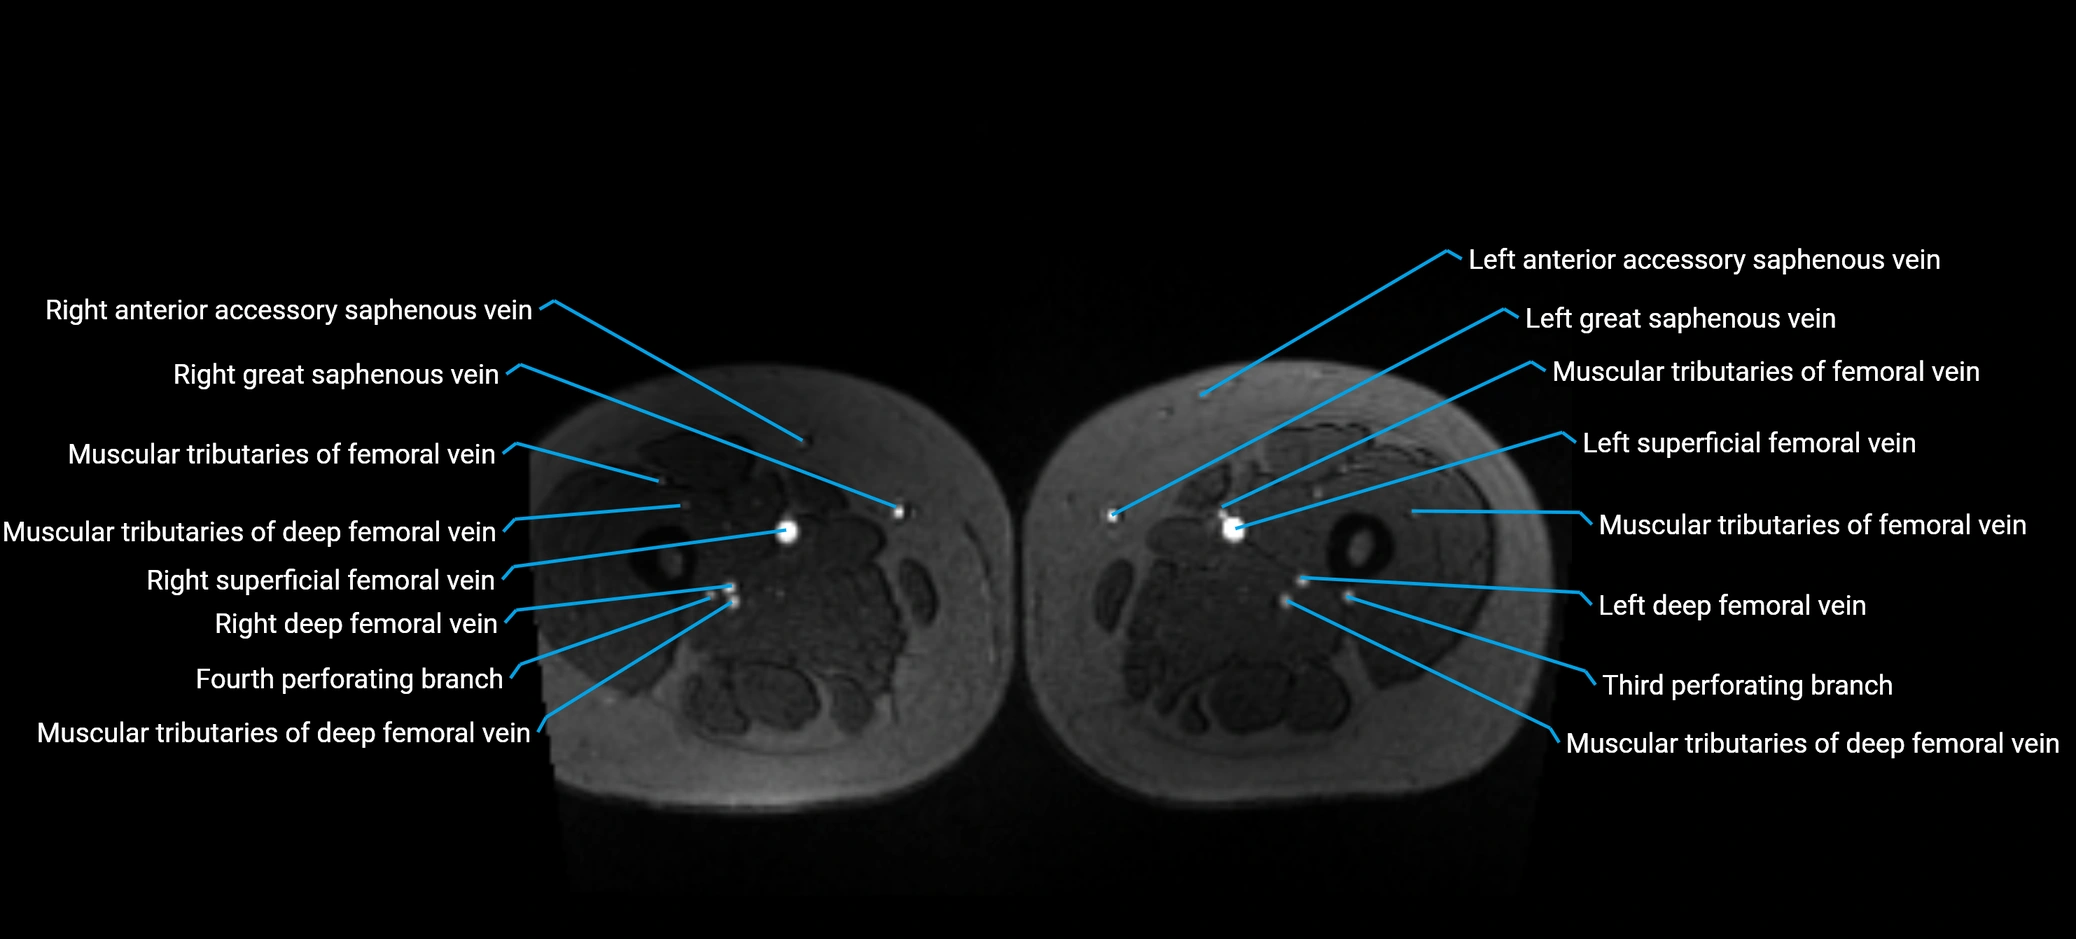

MRI image

image